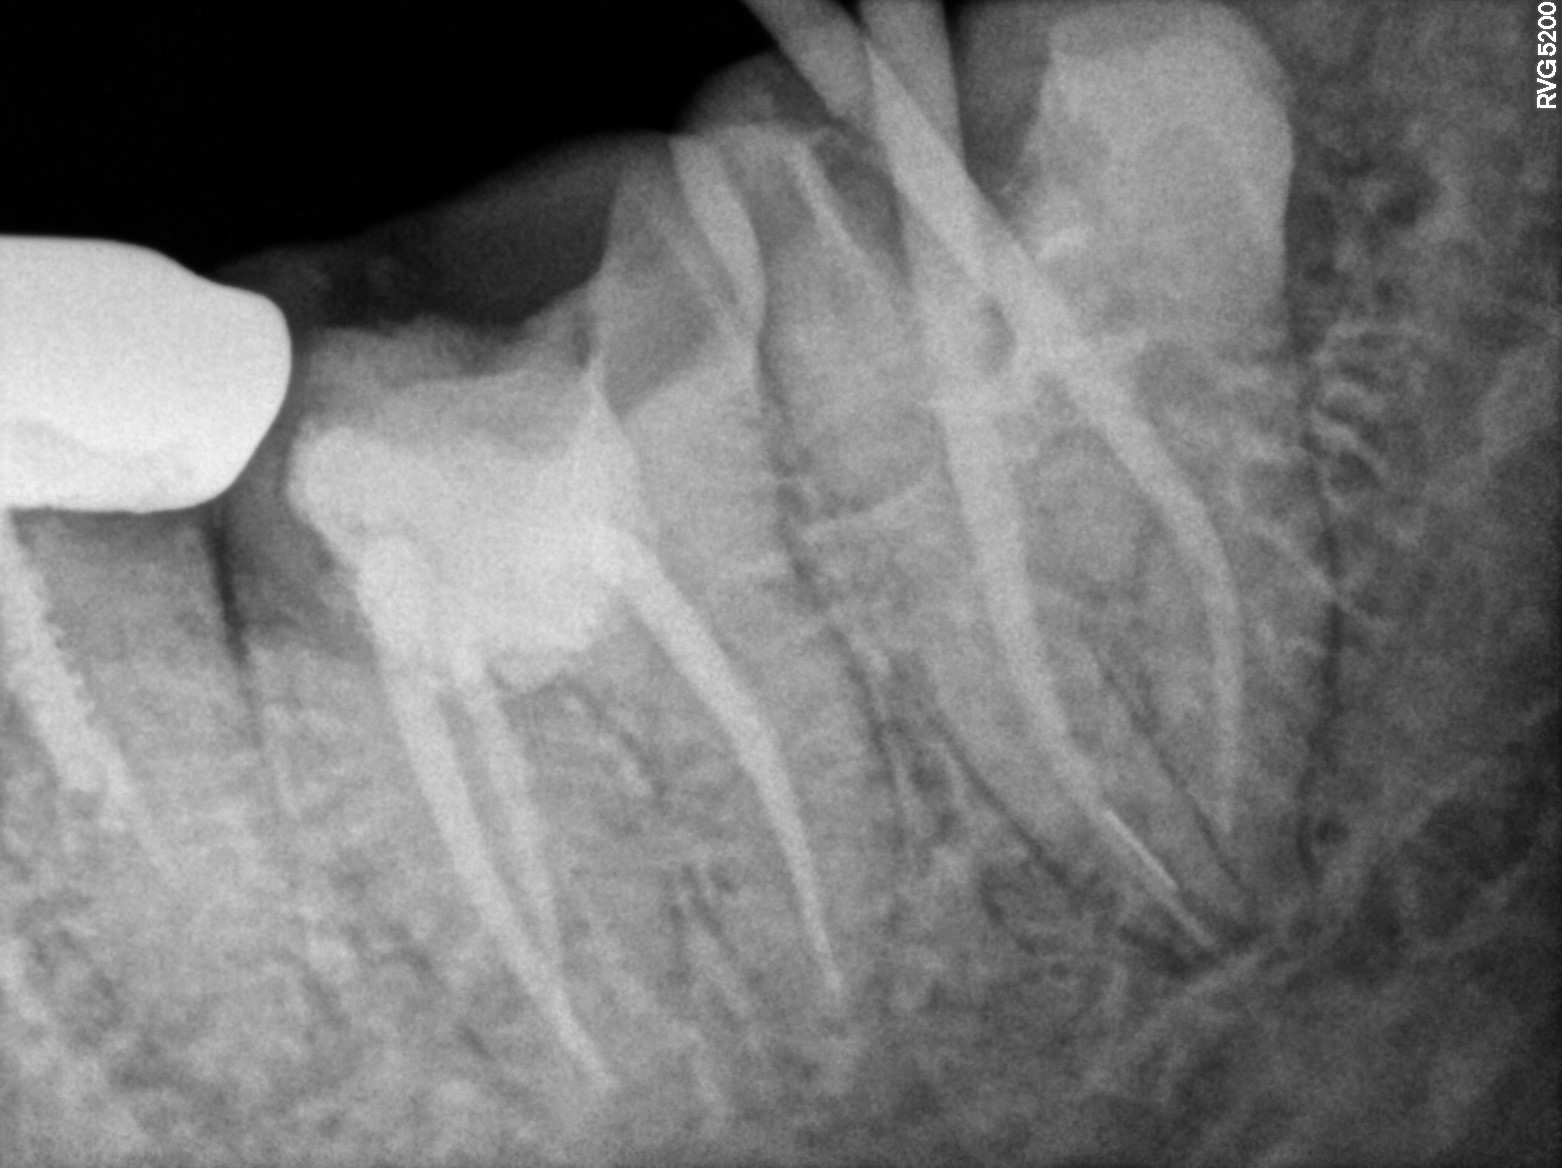

Dental Radiographs FHIR: DocumentReference · LOINC 24641-7

R58.jpg

24641-7